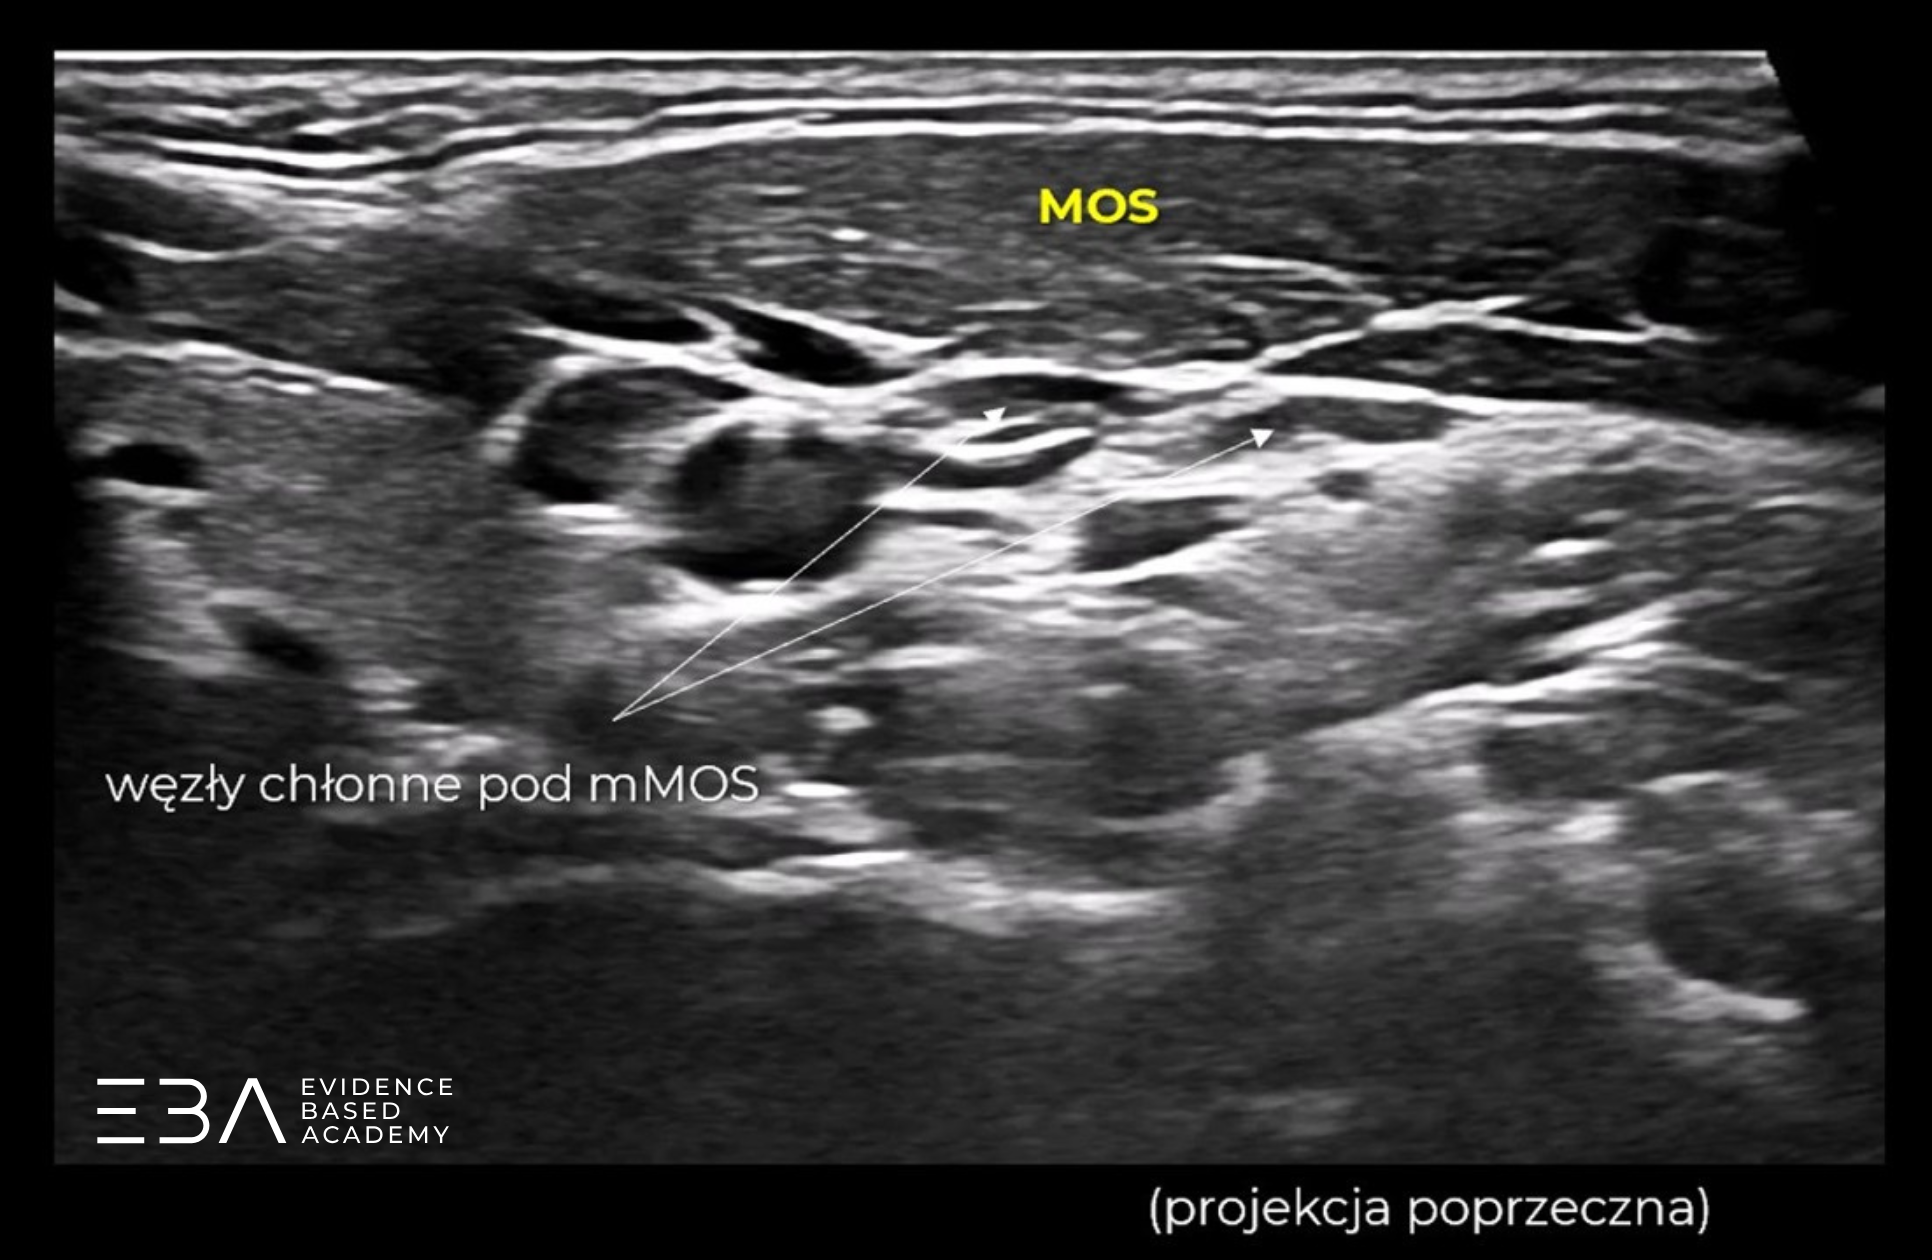

Mięsień MOS w projekcji poprzecznej i podłużnej z zaznaczonymi węzłami chłonnymi.